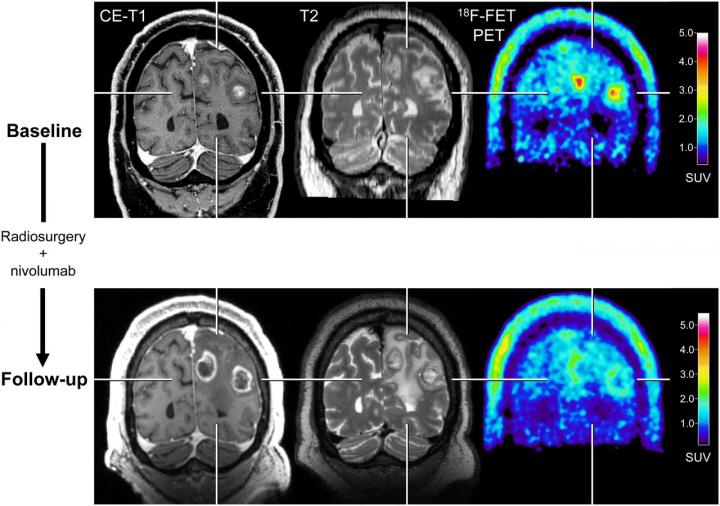

image: After radiosurgery concurrent with nivolumab in 59-year-old patient with melanoma BM (patient 1; Supplemental Tables 3 and 5), F-18 FET PET at follow-up 12 weeks after treatment initiation (bottom row) shows significant decrease of metabolic activity (TBRmean, ?28%) compared with baseline (top row), although MRI changes were consistent with progression according to iRANO criteria. Reduction of metabolic activity was associated with stable clinical course over 10 mo. CE = contrast-enhanced.

Reston, VA--For patients with brain metastases, amino acid positron emission tomography (PET) can provide valuable information about the effectiveness of state-of-the-art treatments. When treatment monitoring with contrast-enhanced magnetic resonance imaging (MRI) is unclear, adding 18F-FET PET can help to accurately diagnose recurring brain metastases and reliably assess patient response. This research was published in The Journal of Nuclear Medicine.

The retrospective study included melanoma and lung cancer patients with brain metastases who had been treated with immune checkpoint inhibitors or targeted therapy alone or in combination with radiotherapy. 18F-FET PET imaging was shown to be a useful method when conventional MRI was inconclusive. It could correctly diagnose brain metastasis relapses and identify patients who were responding to treatment and those who were not.

"In cases of ambiguous MRI findings, supplemental FET PET is helpful for treatment monitoring. It provides physicians with a longer time window for subsequent patient management and allows them to optimize the treatment strategy for each individual patient," noted Galldiks. "Since this approach is so accurate, it has the potential to influence clinical decision making. This may help to reduce the number of invasive procedures and limit overtreatment for a considerable number of seriously ill patients with brain metastases."